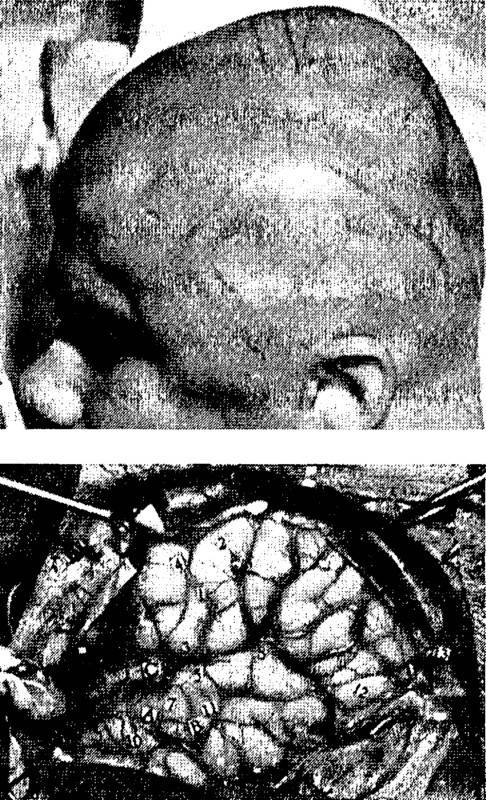

Рис. 1.7. Непосредственная стимуляция мозга вызывает иллюзию реальных ощущений.

Вверху – фотография пациента, подготовленного к операции; над левым ухом намечена линия разреза.

Внизу – поверхность мозга с пронумерованными ярлыками, которыми отмечены участки положительных ответов на стимуляцию.